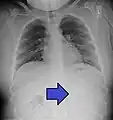

A coin seen on AP CXR in the esophagus

A coin seen on lateral CXR in the esophagus